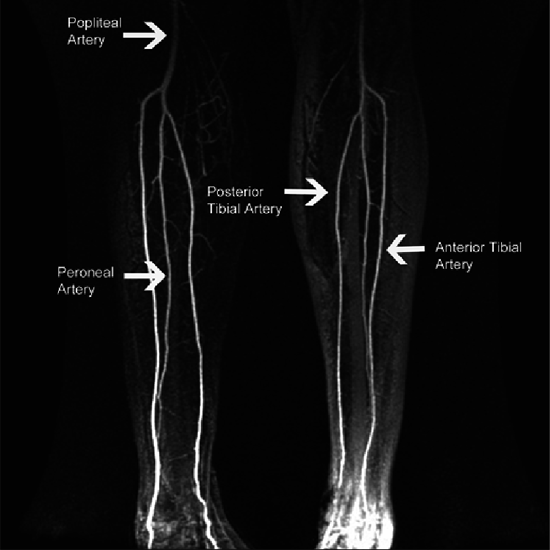

This noninvasive test perfectly helps to assess the situation of peripheral arteries in detail that too without using any kind of sedative, ionised radiation or catheter.

MR Angiography Lower Limb is a Magnetic Resonance Imaging non-invasive medical diagnostic tool for the detection of abnormalities related to the blood vessels of lower limbs. MR Angiography Lower Limb shows blood vessel abnormalities in the lower limbs.